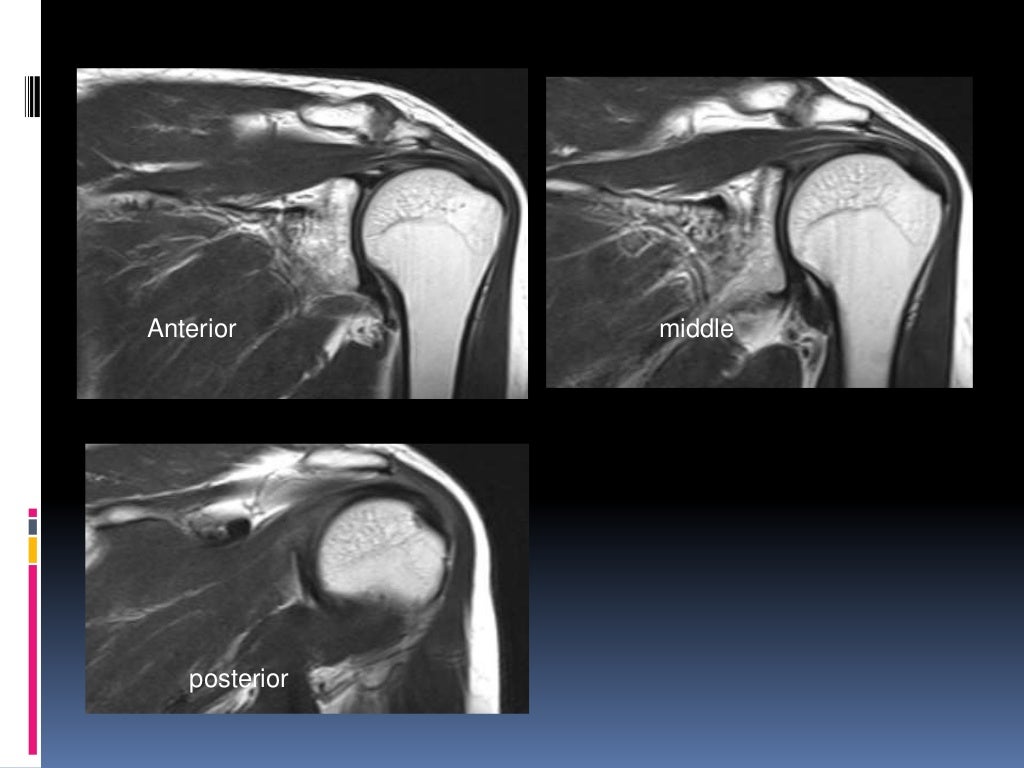

What Is A Shoulder Mri . An mri scan uses magnets and radio waves to capture images of your body’s internal structures. What is a shoulder mri? The mri allows accurate assessment of any pathologic changes of the structures of the shoulder, including the glenoid labrum, the humeral head, the articular. However, the technical jargon in mri reports. What is a shoulder mri scan? Mri of the shoulder is a powerful tool to non invasively diagnose abnormalities of the shoulder. Magnetic resonance imaging (mri) is a critical diagnostic tool used to assess shoulder injuries and conditions. Mri of the shoulder provides detailed images of structures within the shoulder joint, including bones, tendons,. A shoulder mri scan makes it possible to assess not only the condition of the rotator cuff tendons, but also other potential sources of problems,. What is mri of the shoulder?

What is a shoulder mri? A shoulder mri scan makes it possible to assess not only the condition of the rotator cuff tendons, but also other potential sources of problems,. What is mri of the shoulder? Magnetic resonance imaging (mri) is a critical diagnostic tool used to assess shoulder injuries and conditions. An mri scan uses magnets and radio waves to capture images of your body’s internal structures. The mri allows accurate assessment of any pathologic changes of the structures of the shoulder, including the glenoid labrum, the humeral head, the articular. Mri of the shoulder provides detailed images of structures within the shoulder joint, including bones, tendons,. Mri of the shoulder is a powerful tool to non invasively diagnose abnormalities of the shoulder. However, the technical jargon in mri reports. What is a shoulder mri scan?

What Is A Shoulder Mri Mri of the shoulder provides detailed images of structures within the shoulder joint, including bones, tendons,. Mri of the shoulder provides detailed images of structures within the shoulder joint, including bones, tendons,. A shoulder mri scan makes it possible to assess not only the condition of the rotator cuff tendons, but also other potential sources of problems,. What is a shoulder mri? However, the technical jargon in mri reports. What is a shoulder mri scan? What is mri of the shoulder? The mri allows accurate assessment of any pathologic changes of the structures of the shoulder, including the glenoid labrum, the humeral head, the articular. Mri of the shoulder is a powerful tool to non invasively diagnose abnormalities of the shoulder. An mri scan uses magnets and radio waves to capture images of your body’s internal structures. Magnetic resonance imaging (mri) is a critical diagnostic tool used to assess shoulder injuries and conditions.

MRI Shoulder How we do it How is MRI Shoulder done at Mater Dei Hospital What Is A Shoulder Mri What is mri of the shoulder? The mri allows accurate assessment of any pathologic changes of the structures of the shoulder, including the glenoid labrum, the humeral head, the articular. Mri of the shoulder is a powerful tool to non invasively diagnose abnormalities of the shoulder. Mri of the shoulder provides detailed images of structures within the shoulder joint, including. What Is A Shoulder Mri.

MRI Shoulder Musculoskeletal Imaging What Is A Shoulder Mri What is a shoulder mri scan? An mri scan uses magnets and radio waves to capture images of your body’s internal structures. Mri of the shoulder is a powerful tool to non invasively diagnose abnormalities of the shoulder. However, the technical jargon in mri reports. A shoulder mri scan makes it possible to assess not only the condition of the. What Is A Shoulder Mri.